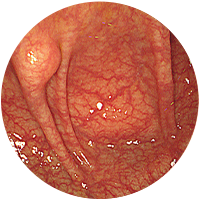

-

2

진행성대장암